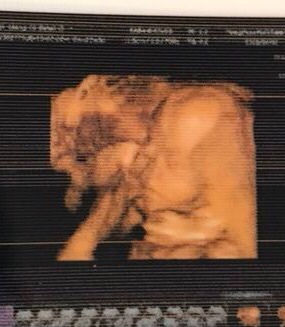

宝宝1个月21天

孕22周+0天

睡觉野蛮是个什么睡姿???!!😳😳😳

Edith MD[帖主]:不受控制 除了不爬着什么姿势都有